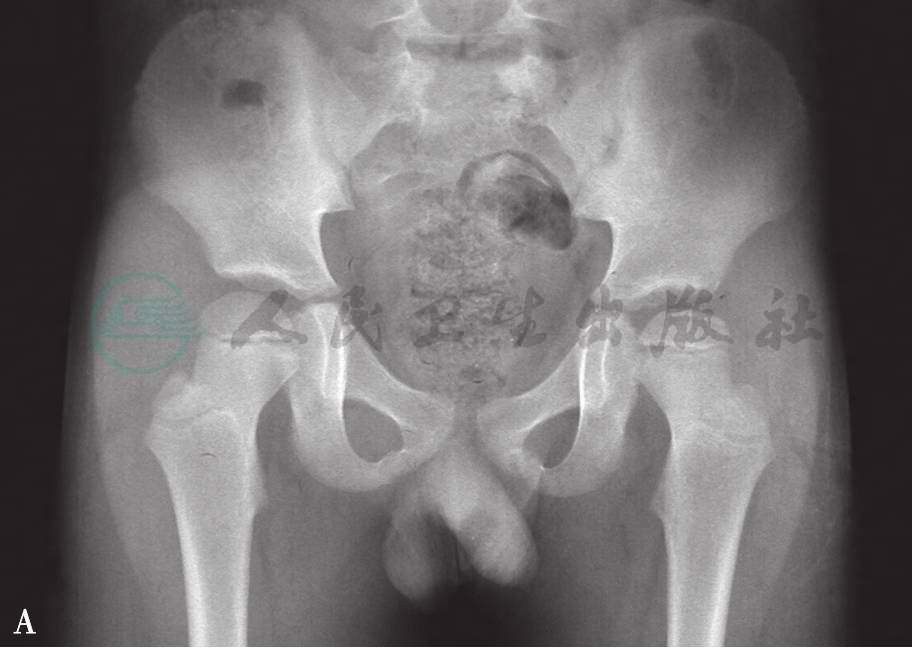

图6

A.男8岁,双股骨头缺血坏死,右侧处于致密期;B.右侧股骨头碎裂、密度不均一、形态不整且塌陷。干骺端可见囊变;C.双侧股骨头碎裂均有融合、密度趋向均匀、形态仍然不规整;左股骨头膨大、但轮廓仍呈圆弧且与髋臼相适应;D.左侧发病后4年、右侧发病后3.5年。双侧股骨头骨小梁纹理正常、骨质密度均匀;虽均有膨大、存在覆盖不良,但轮廓与髋臼形态适应